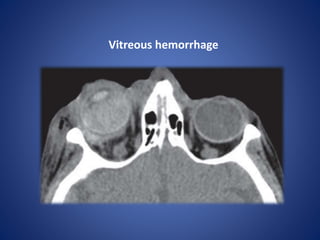

Vitreous hemorrhage

• #23 81-yearold woman receiving anticoagulation therapy, who presented after a trauma, shows an extensive vitreous hemorrhage.